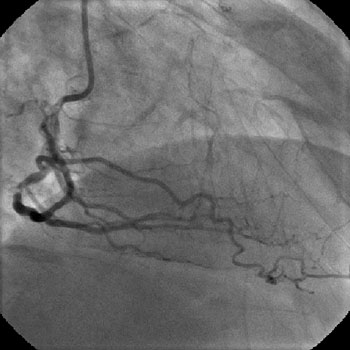

3) LAD: Ostial CTO ( Figure 2) with collaterals from RCA and LCX (Figure 3).